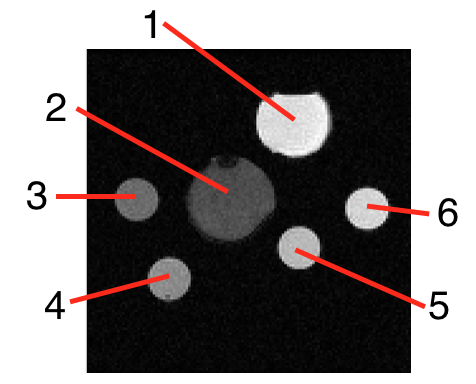

Images of bottles of size were collected with a field of view of cm using a kHz receiver bandwidth with a kHz receiver bandwidth and a mm slice thickness. Data was collected of an axial slice of a set of bottles as shown in Fig. 2. The bottles were filled with manganese chloride, copper sulfate, or emulsified peanut oil in carrageenan gel as specified in Fig. 2a. Peanut oil was used to simulate fat; it has a similar Larmor frequency. The percentages of peanut oil in bottles , , , and by volume (prior to curing) were , , , and , respectively. The bottles were separated with MR compatible padding. A single-channel quadrature birdcage head coil was used for both excitation and reception.

Figure 4 shows the quantitative values estimated from the data of Fig. 3 using the methods described in section 2.2. The bright regions in the fat fraction map for bottles , , and are due to regions of the mask that exceed the actual data. Note that the fat fraction of bottles , , and are all approximately , as expected.

It is not expected that the fraction of signal due to fat equals the fat fraction volume (due to differences in the molar mass, differences in the number of hydrogen atoms per mole, and the chemical shielding of the fat molecule). However, it is expected that the fraction of signal due to fat is proportional to the percentage of fat in the voxel. We verify this in the fat fraction of the bottles estimated by comparing the ratios of different bottles as shown in Table 2. The ratio of signal intensities is approximately equal to the ratio of fat fraction per volume. This validates the fat fraction estimate attained by multiMap.

| : | = | = | |

| : | = | = |